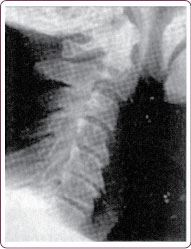

Бывает, наоборот, шейный изгиб излишне спрямляется (рис. 6).

Рис. 6. Спрямление шейного отдела позвоночника